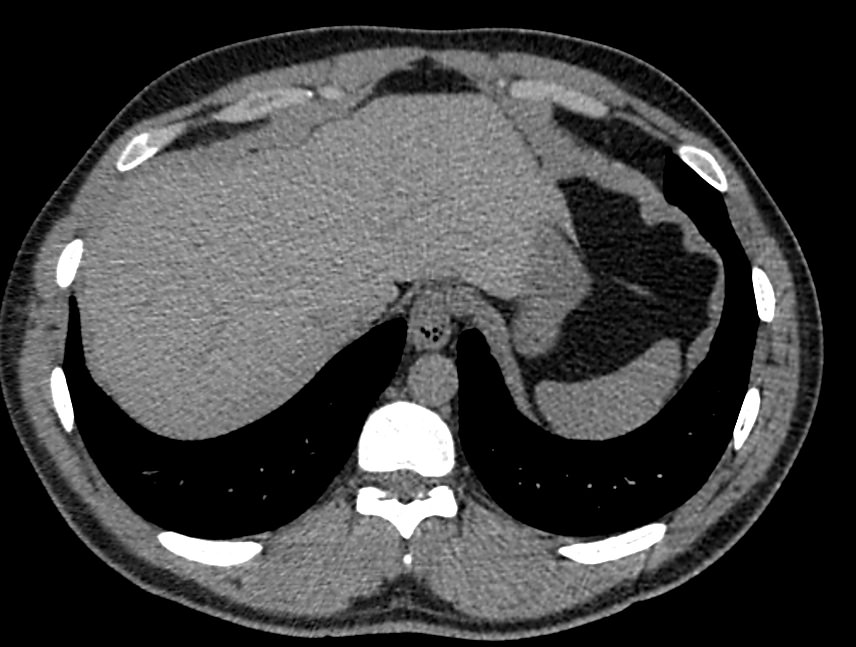

Печеночная ткань имеет обильное кровоснабжение, поэтому часто ультразвуковая диагностика заболеваний печени затруднена. Одним из наиболее информативных методов диагностики является мультиспиральная КТ печени, которая может проводиться в стандартном режиме и с внутривенным болюсным контрастированием. Введение йодсодержащего контрастного вещества значительно повышает диагностическую ценность компьютерной томографии и позволяет, в частности, выявить злокачественное образование на ранней стадии, отличить доброкачественный процесс от злокачественного, визуализировать изменения внутрипеченочных желчных протоков и многие другие патологические процессы.

В нашей клинике сканирование печени выполняется на современном 128-срезовом томографе экспертного класса TOSHIBA AQUILION CXL, который производит послойное сканирование исследуемого органа с последующей цифровой обработкой полученных данных для создания трехмерных изображений печени высокого качества и контрастности. Увеличенное количество детекторов, вмонтированных в аппарат, обеспечивает быстрое время исследования и пониженные дозы рентгеновского излучения, получаемого пациентом.

Мультиспиральная компьютерная томография является быстрым высокоточным и доступным методом исследования, позволяющим обнаружить тяжелые заболевания на ранних стадиях, поставить точный и достоверный диагноз и назначить своевременное лечение.